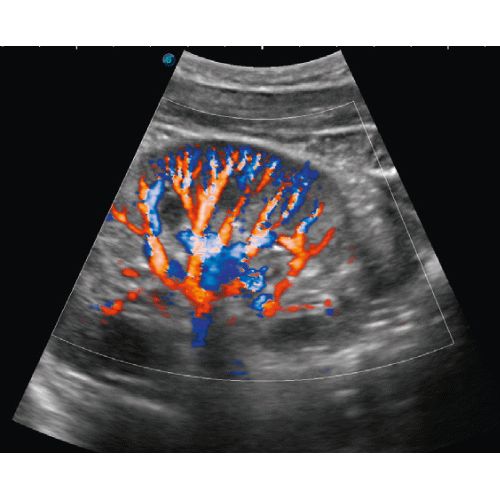

SonidoSmart Pro to zaawansowany technologicznie, w pełni autonomiczny system ultrasonograficzny, który redefiniuje mobilną diagnostykę obrazową w gabinetach medycyny estetycznej, fizjoterapii i urologii. W przeciwieństwie do uproszczonych skanerów kieszonkowych, SonidoSmart Pro jest kompletnym urządzeniem dedykowanym do pracy profesjonalnej, zapewniającym najwyższą jakość obrazowania struktur podskórnych, naczyń krwionośnych oraz tkanek miękkich bez konieczności korzystania z zewnętrznych aplikacji czy urządzeń mobilnych.

Jako profesjonalny mobilny aparat USG, system ten został zoptymalizowany pod kątem maksymalnego bezpieczeństwa zabiegowego. W medycynie estetycznej pozwala na błyskawiczne mapowanie przebiegu tętnic i żył przed podaniem wypełniaczy, co jest kluczowe w profilaktyce okluzji naczyniowych. Dzięki wysokiej częstotliwości pracy sondy liniowej, lekarz otrzymuje krystalicznie czysty obraz w czasie rzeczywistym, umożliwiający precyzyjną lokalizację depozytów preparatów lub ocenę stanów zapalnych. Urządzenie charakteryzuje się wyjątkową ergonomią – jest lekkie, poręczne i gotowe do pracy w kilka sekund od uruchomienia. Brak polegania na zewnętrznym oprogramowaniu gwarantuje stabilność transmisji obrazu i pełną ochronę dokumentacji medycznej pacjenta, czyniąc z SonidoSmart Pro niezawodne narzędzie w rękach wymagającego specjalisty.

• Bezpieczeństwo naczyniowe: Precyzyjne obrazowanie w trybie Dopplera pozwala uniknąć przypadkowych iniekcji donaczyniowych.

• Tryby pracy: B-Mode, M-Mode, Color Doppler, Power Doppler, PW.

• Częstotliwość sondy: 10 - 16 MHz: sonda liniowa zoptymalizowana pod kątem struktur powierzchownych.